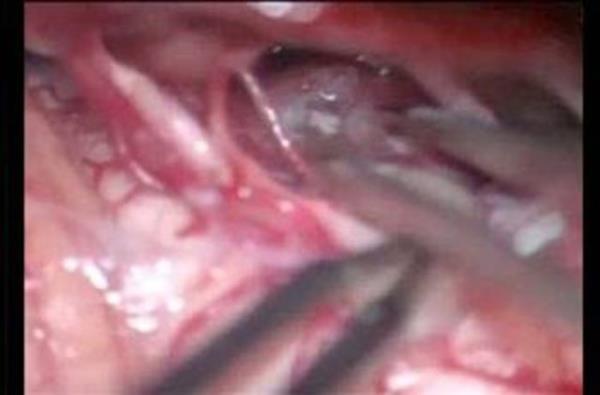

13. Kahramanmaraş'ın Afşin ilçesinde bir genç kız, karın ağrısı şikayetiyle gittiği hastanede, midesinde çatal olduğunu öğrenince şok oldu. Genç kızın çatalı küçük yaşta yuttuğu sanılırken, çatal başarılı bir ameliyatla çıkarıldı.

Kahramanmaraş'ın Afşin ilçesinde bir genç kız, karın ağrısı şikayetiyle gittiği hastanede, midesinde çatal olduğunu öğrenince şok oldu. Genç kızın çatalı küçük yaşta yuttuğu sanılırken, çatal başarılı bir ameliyatla çıkarıldı.